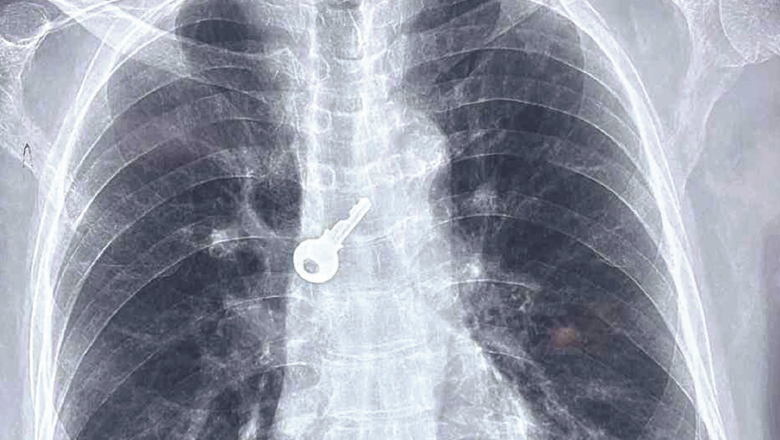

വ​യോ​ധി​ക​ന്‍റെ ശ്വാ​സ​നാ​ള​ത്തി​ൽ താ​ക്കോ​ൽ; ആ​ല​പ്പു​ഴ മെ​ഡി​ക്ക​ൽ കോ​ള​ജ് ആ​ശു​പ​ത്രി ബ്രോ​ങ്കോ​സ്കോ​പ്പി​യി​ലൂ​ടെ പു​റ​ത്തെ​ടു​ത്തു; ആ​രോ​ഗ്യ​വാ​നാ​യി ചെ​ല്ല​പ്പ​ൻ​പി​ള്ള

വ​യോ​ധി​കന്‍റെ ശ്വാ​സ​നാ​ള​ത്തി​ൽ കു​ടു​ങ്ങി​യ താ​ക്കോ​ൽ ബ്രോ​ങ്കോ സ്കോ​പ്പി പ​രി​ശോ​ധ​ന​യി​ലൂ​ടെ പു​റ​ത്തെ​ടു​ത്ത് ആ​ല​പ്പു​ഴ മെ​ഡി​ക്ക​ൽ കോ​ള​ജ് ആ​ശു​പ​ത്രി ഡോ​ക്ട​ർ​മാ​ർ. ഹ​രി​പ്പാ​ട് ല​ക്ഷ്മി ഭ​വ​ന​ത്തി​ൽ ചെ​ല്ല​പ്പ​ൻ​പി​ള്ള (77)യു​ടെ ശ്വാ​സ​നാ​ള​ത്തി​ൽ കു​ടു​ങ്ങി​യ താ​ക്കോ​ലാ​ണ് ര​ണ്ടു മ​ണി​ക്കൂ​ർ നീ​ണ്ട ബ്രോ​ങ്കോ സ്കോ​പ്പി വ​ഴി പു​റ​ത്തെ​ടു​ത്ത​ത്.

ചൊ​വ്വാ​ഴ്ച വീ​ട്ടി​ൽ ബോ​ധ​മ​റ്റു വീ​ണ ചെ​ല്ല​പ്പ​ൻപി​ള്ള​യെ വീ​ട്ടു​കാ​ർ ഉ​ട​ൻ മെ​ഡി​ക്ക​ൽ കോ​ള​ജ് ആ​ശു​പ​ത്രി​യി​ൽ എ​ത്തി​ക്കു​ക​യാ​യി​രു​ന്നു. ശ്വാ​സ​ത​ട​സ​വും ചു​മ​യും അ​നു​ഭ​വ​പ്പെ​ട്ട ഇ​ദ്ദേ​ഹ​ത്തെ ഉ​ട​ൻ എ​ക്സ്റേ ​പ​രി​ശോ​ധ​ന​യ്ക്ക് വി​ധേ​യ​നാ​ക്കി​യ​പ്പോ​ഴാ​ണ് താ​ക്കോ​ൽ ശ്വാ​സ​നാ​ള​ത്തി​ൽ കു​ടു​ങ്ങി​യ നി​ല​യി​ൽ ക​ണ്ടെ​ത്തി​യ​ത്.

ഉ​ട​ൻ മ​റ്റ് ആ​രോ​ഗ്യ പ​രി​ശോ​ധ​ന​ക​ളെ​ല്ലാം പൂ​ർ​ത്തി​യാ​ക്കി​യ ചെ​ല്ല​പ്പ​ൻപി​ള്ള​യെ ബു​ധ​നാ​ഴ്ച ബ്രോ​ങ്കോ സ്കോ​പ്പി​ക്ക് വി​ധേ​യ​നാ​ക്കു​ക​യാ​യി​രു​ന്നു.എ​ന്നാ​ൽ, താ​ക്കോ​ൽ എ​ങ്ങ​നെ ഉ​ള്ളി​ൽ പോ​യെ​ന്ന് അ​റി​യി​ല്ലെ​ന്ന് ചെ​ല്ല​പ്പ​ൻപി​ള്ള പ​റ​ഞ്ഞു. പു​റ​ത്തെ​ടു​ത്ത താ​ക്കോ​ൽ അ​ടു​ത്ത ദി​വ​സ​ങ്ങ​ളി​ൽ ഉ​ള്ളി​ൽ പോ​യ​ത​ല്ലെ​ന്നും മാ​സ​ങ്ങ​ളു​ടെ പ​ഴ​ക്ക​മു​ണ്ടെ​ന്നും ഡോ​ക്ട​ർ​മാ​ർ പ​റ​ഞ്ഞു.

കാ​ർ​ഡി​യോ വാ​സ്കു​ല​ർ സ​ർ​ജ​ൻ ഡോ. ​ആ​ന​ന്ദ​ക്കു​ട്ട​ൻ, അ​ന​സ്തേ​ഷ്യ വി​ഭാ​ഗം പ്ര​ഫ​സ​റും ആ​ശു​പ​ത്രി സൂ​പ്ര​ണ്ടു​മാ​യ ഡോ. ​എ.​ ഹ​രി​കു​മാ​ർ, അ​ന​സ്തേ​ഷ്യ വി​ഭാ​ഗം പ്ര​ഫ​സ​ർ ഡോ. ​വി​മ​ൽ​പ്ര​ദീ​പ്, ജൂ​ണിയ​ർ റ​സി​ഡ​ന്‍റ് ഡോ. ​ജോ​ജി ജോ​ർ​ജ് എ​ന്നി​വ​ർ ഉ​ൾ​പ്പെ​ട്ട സം​ഘ​മാ​ണ് താ​ക്കോ​ൽ പു​റ​ത്തെ​ടു​ത്ത​ത്. ആ​രോ​ഗ്യ നി​ല തൃ​പ്തി​ക​ര​മാ​യ​തി​നാ​ൽ ഇ​ദ്ദേ​ഹ​ത്തെ ഡി​സ്ചാ​ർ​ജ് ചെ​യ്തു.